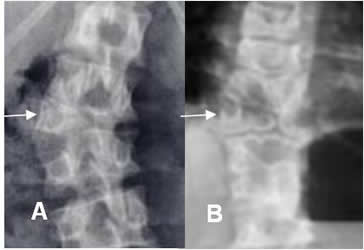

Fig 39. Progresión.

A y B: Rx AP. Escoliosis dorsolumbar derecha que ha progresado, después de 2 años de seguimiento.